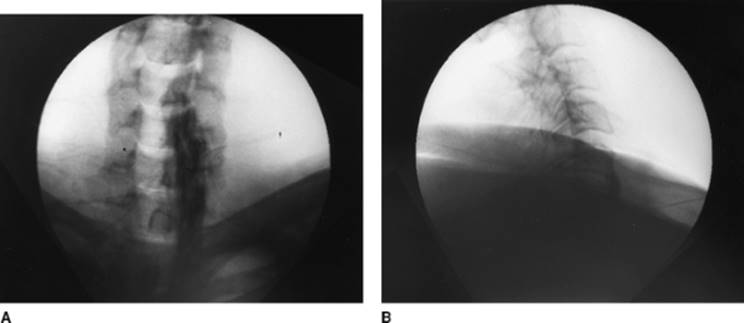

Approach and Technique: The lumbar region is prepared and draped using sterile techniques. The block is performed at the L3 level. The fluoroscopy beam is rotated 25° to 30° lateral to the midline toward the side to be blocked, and a fluoroscopic view is obtained. The upper lateral edge of the L3 vertebra is then isolated by keeping a sterile clamp tip at that point on the skin, and local anesthesia is applied to the skin and underlying tissues (Fig. 63-6A). The bent 22-gauge spinal needle is then introduced under the skin with the tip pointing laterally. The needle is advanced gradually toward the upper lateral border of L3 with the bevel pointing laterally. The lateral (Fig. 63-6B) and anteroposterior (Fig. 63-6C) views are taken to confirm the depth of the needle and its distance from the midline. The needle is advanced until it approaches the anterolateral margin of the vertebral body in the lateral view, taking care that the needle does not cross the facet line in the anteroposterior view. The bevel is then directed medially to hug the vertebral body anterolaterally. After negative aspiration for blood and cerebrospinal fluid, 5 mL of Isovue-200 is injected. After confirming spread of the dye in anteroposterior and lateral views, 5 mL of 0.5% bupivacaine is injected. Temperature recordings are obtained 5 to 10 minutes after the block and compared with the temperatures before.

Figure 63-6. Lumbar sympathetic block.